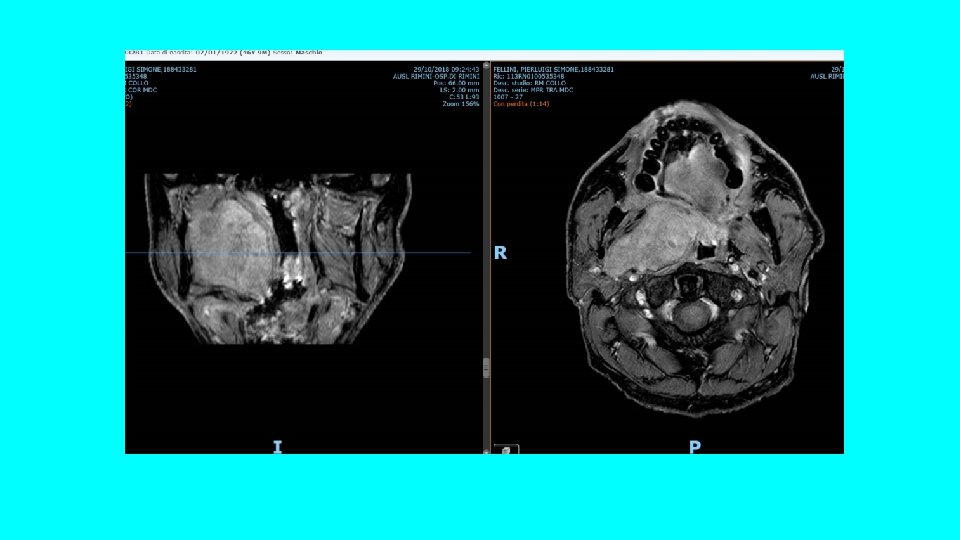

CASO CLINICO • Uomo, 47 anni • Comorbilità: sindrome ansiosa, seguito dalla neurologia per cefalea ricorrente • Clinica: sensazione di fastidio in gola da diverso tempo, in particolar modo durante la deglutizione.

ESAME OBIETTIVO Ugola ? ? ? Loggia tonsillar e sinistra

RADIOLOGIA: RMN